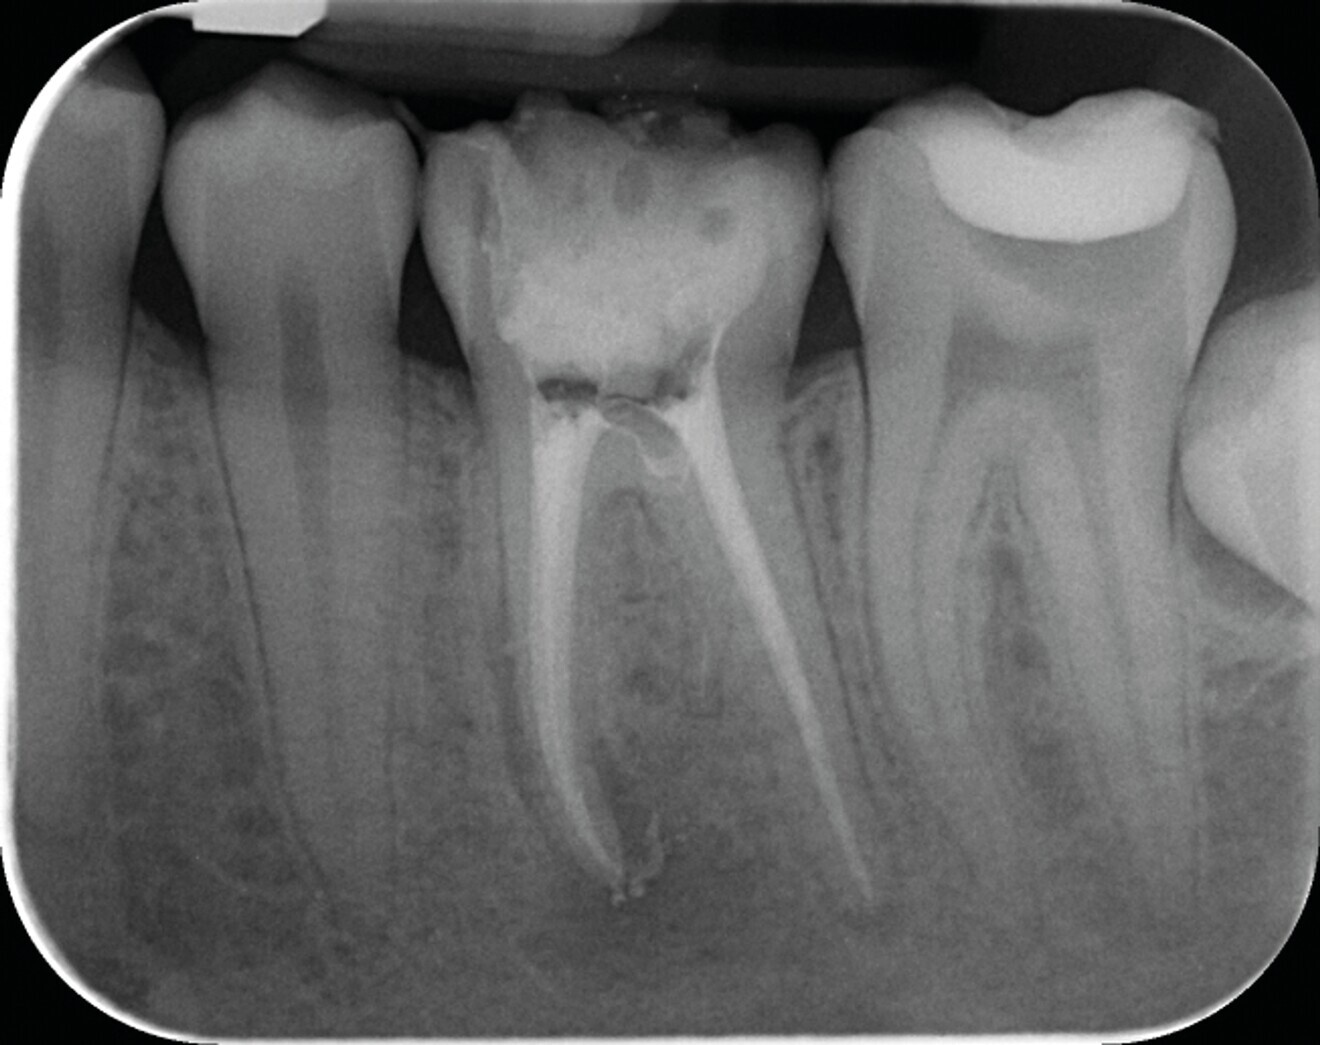

Fig. 1a : Radiographie pré-opératoire d’une molaire maxillaire (16) présentant une lésion apicale sur la racine mésio vestibulaire. Le retraitement a consisté à éliminer le matériau présent dans les canaux, récupérer la perméabilité du canal de la racine MV et gérer la fausse route faite lors du traitement précédent.

Fig.1b : La radiographie post-opératoire objective une atteinte des objectifs techniques (obturation Bioroot RCS (Septodont).

Fig. 1c : La radiographie de contrôle à un an, confirme l’efficacité du traitement par la régénération osseuse.